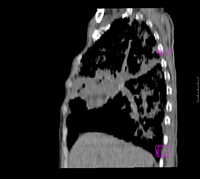

女67岁,咳嗽咯白痰伴纳差一月。右肺呼吸音低可闻及湿罗音。白细胞及淋巴细胞不高,无发烧

1、右上胸廓塌陷,纵隔气管右移

2、病灶靠后方,一般结核多见一点

3、病灶内,纵隔内有少许钙化灶

3楼的肺细支气管肺泡癌也不能完全排除,毕竟患者年纪大,病史短,临床上感染症状不明显,建议短期内复查吧